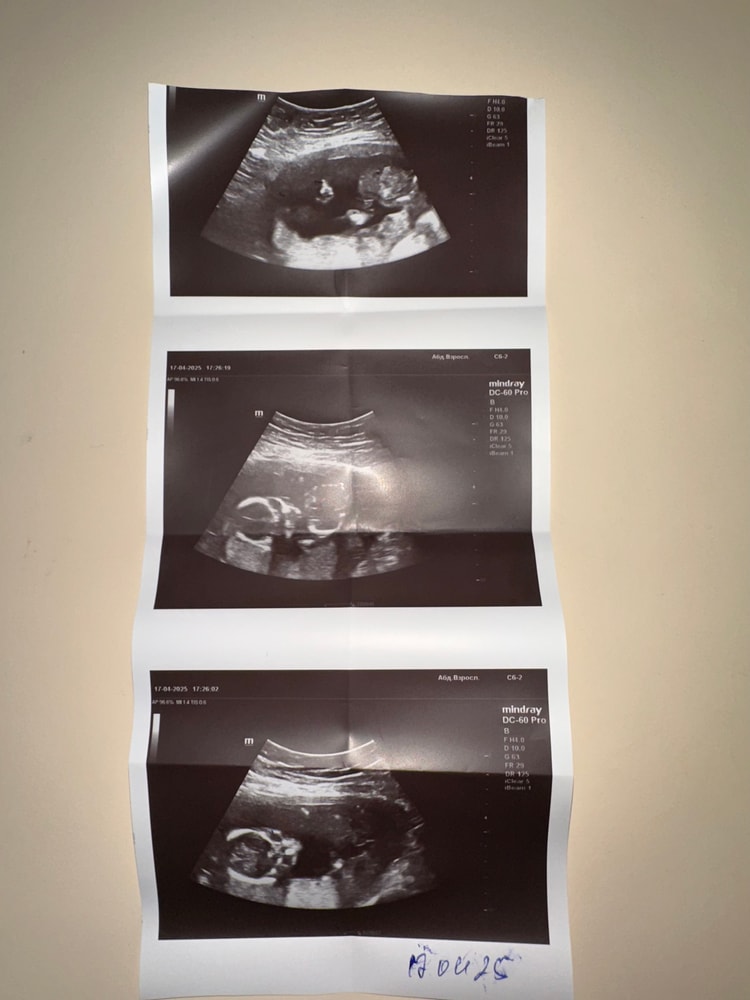

Здравствуйте девочки, срок 15,4 дня была на узи, покрутила по животу минут 5 в итоге сказала, что девочка. Помогите пожалуйста хотя бы как-то определить по фото, не совсем понятно. Я лично по фото не могу понять, как она там увидела девочку, или же срок еще маленький, решили что там девочка… хочу еще в 20 недель пойти сделать чтоб точно быть уверена.

Вы сами то понимаете, что здесь на фото?)) нет там половых органов) сейчас через экран прочувствую какой пол)

интересный конечно ракурс ваша врач выбрала для фото)))

обычно хотя бы в профиль фоткают))

Пола, понятное дело тут не видно)) тут личико ребенка, которое смотрит прямо на датчик практически)